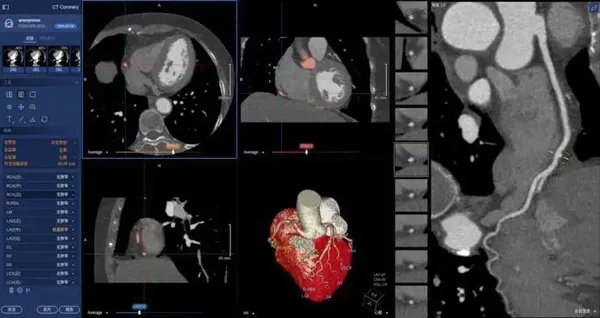

02、在醫學上的應用

在醫學領域,機器視覺主要用于醫學輔助診斷。首先采集核磁共振、超聲波、激光、X射線、γ射線等對人體檢查記錄的圖像,再利用數字圖像處理技術、信息融合技術對這些醫學圖像進行分析、描述和識別,最后得出相關信息,對輔助醫生診斷人體病源大小、形狀和異常,并進行有效治療發揮了重要的作用。不同醫學影像設備得到的是不同特性的生物組織圖像,如X射線反映的是骨骼組織,核磁共振影像反映的是有機組織圖像,而醫生往往需要考慮骨骼有機組織的關系,因而需要利用數字圖像處理技術將兩種圖像適當地疊加起來,以便于醫學分析。